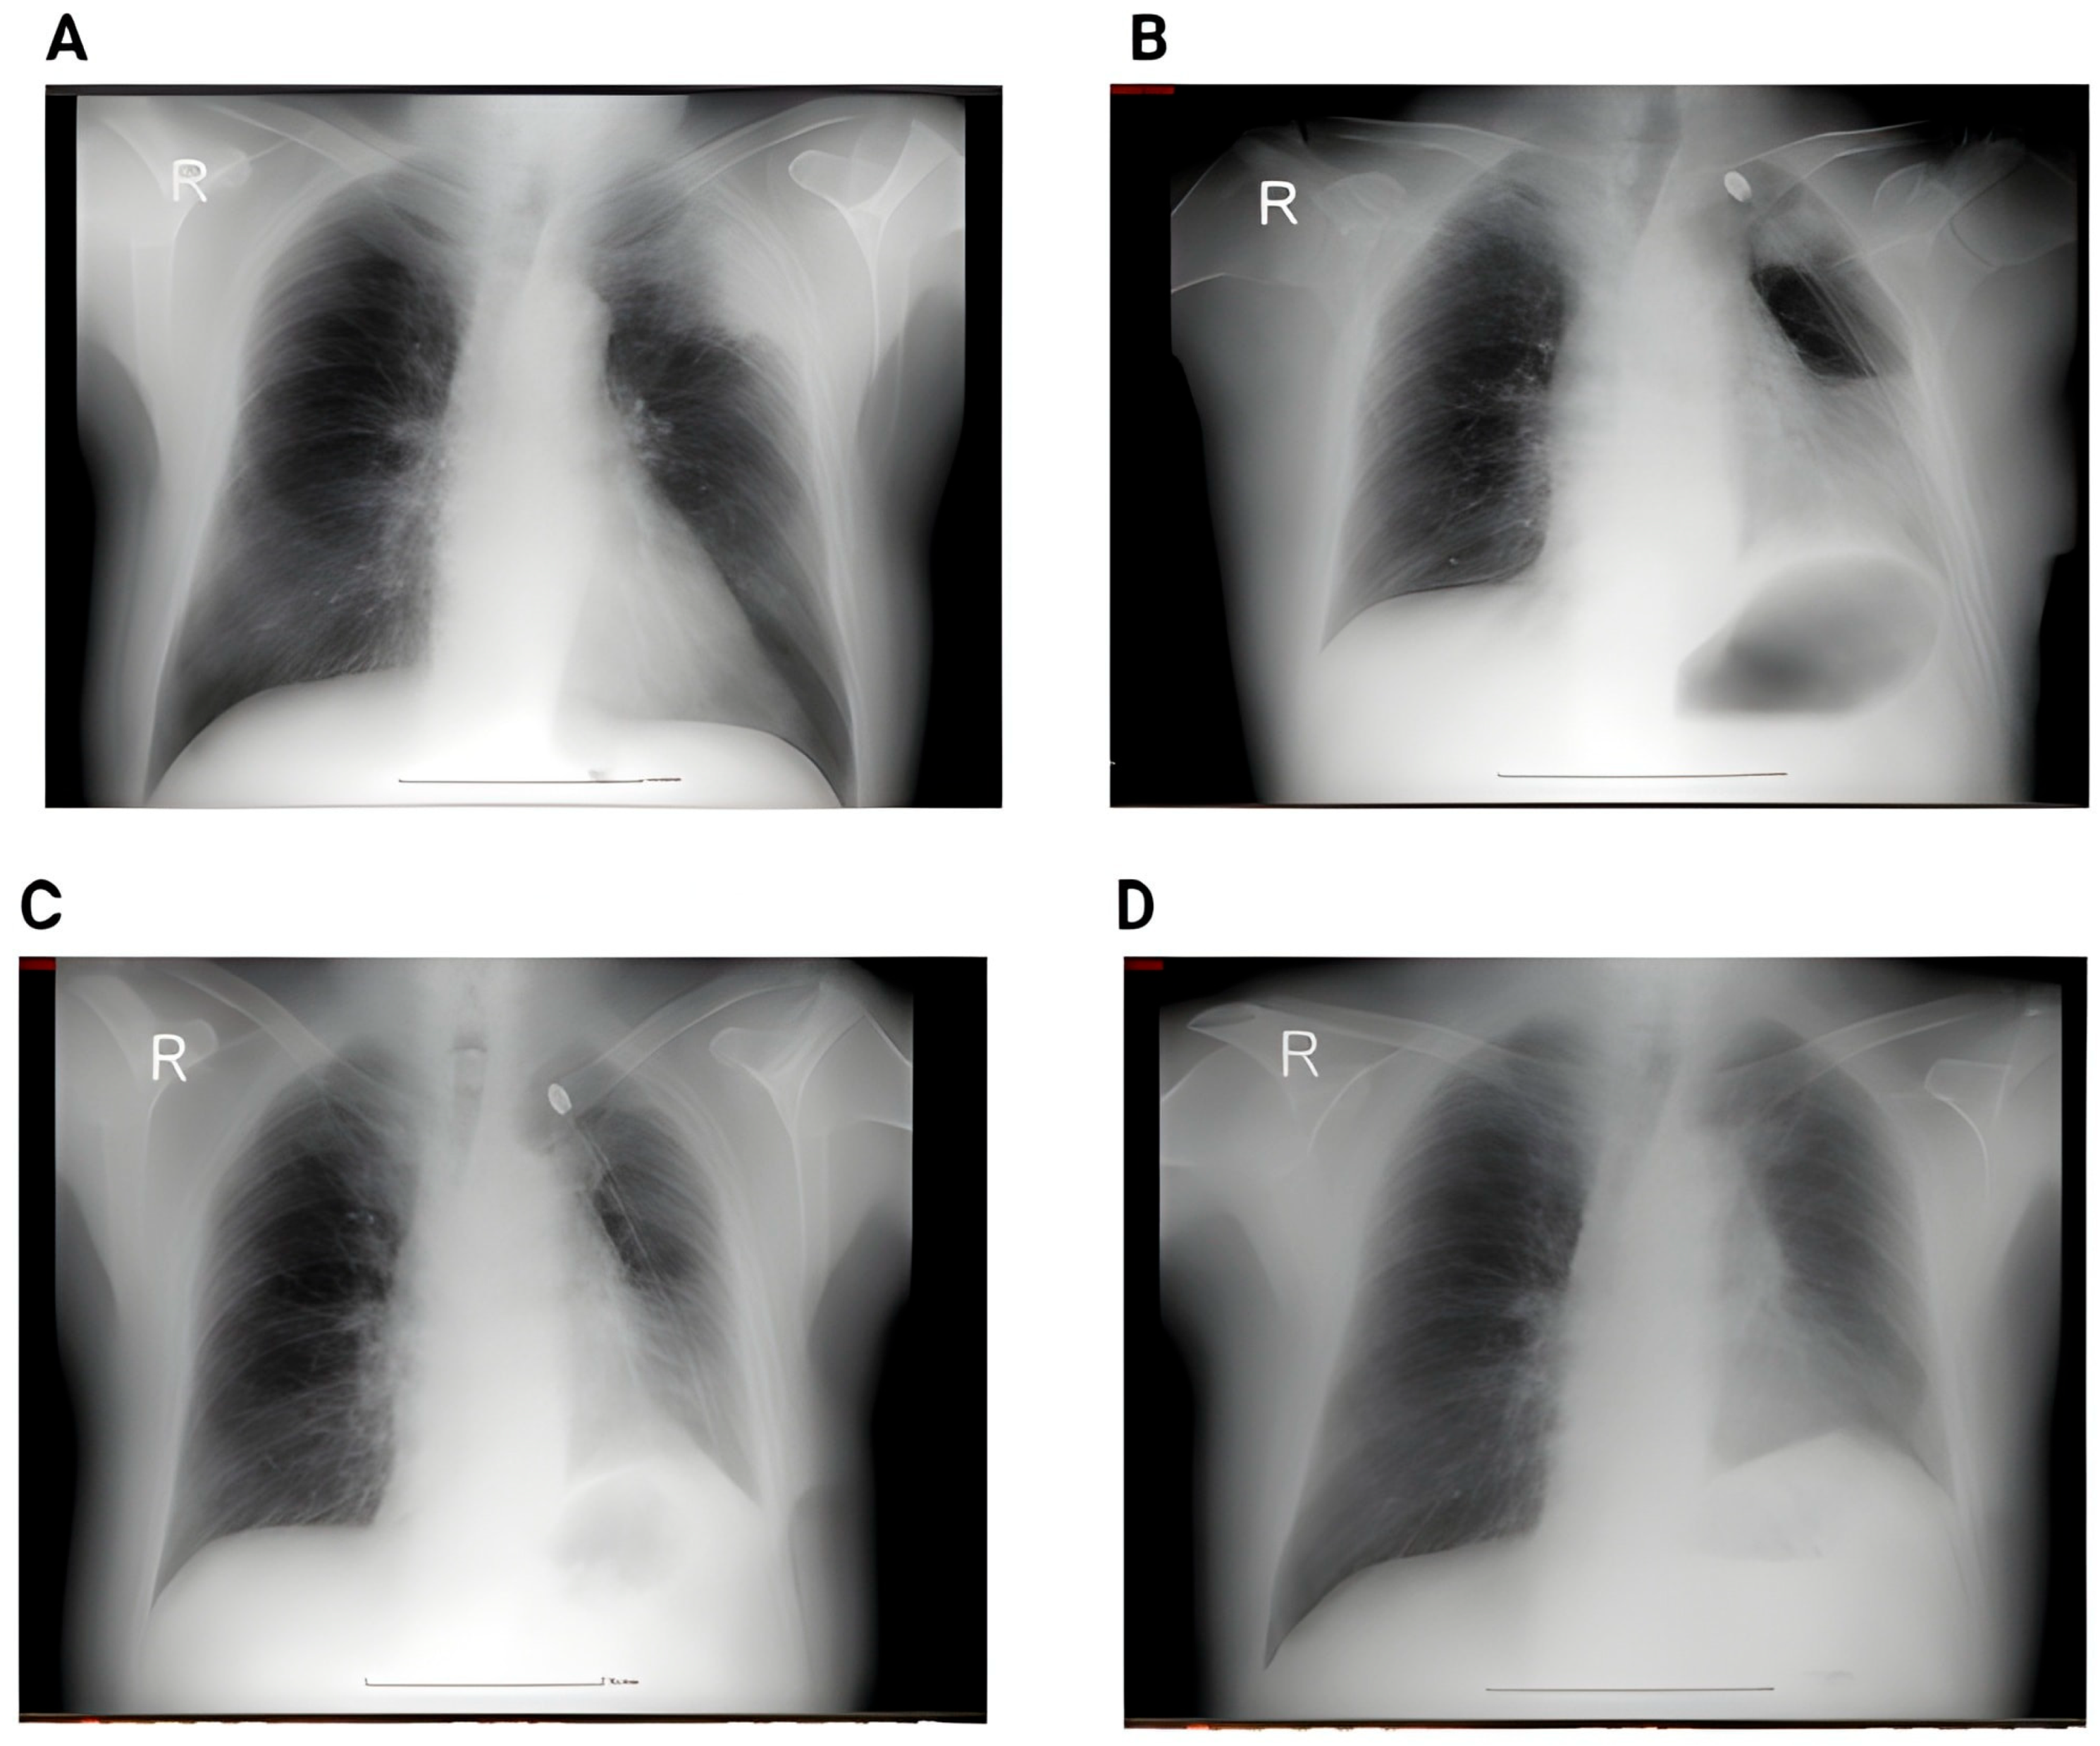

Representative imaging examples are provided in Figure 5 to illustrate the spectrum of radiological changes observed before and after lobectomy.

Figure 5. (A) Preoperative image showing a large nodule in the middle lobe. (B) 2nd day postoperative x-ray showing small right pleural effusion, right basal infiltrates and bilateral basal atelectasis. (C) CT acquisition immediately after showing right pleural effusion, perihilar consolidation and ground-glass opacities, passive atelectasis. (D) One month postoperative showing full resolution of the postoperative complications after conservative therapy—no reintervention.